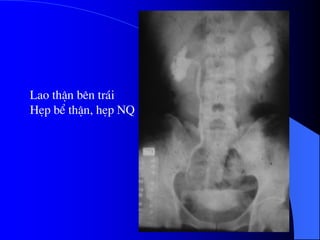

2.3.3. Lao tháûn

- ASP: hçnh väi hoaï cháút baî âáûu caïc cuí lao åí

giai âoaûn ráút muäün (tháûn mastic) - hiãúm.

- NÂTM âuïng kyî thuáût gåüi yï cháøn âoaïn:

+ Hçnh ràng cæa doüc theo âæåìng dáùn tiãøu do

caïc äø loeït nhoí.

+ Heûp cäø âaìi tháûn, âaìi tháûn daîn thaình hçnh ly

ræåüu hoàc hçnh cáöu, hçnh gai åí bãø tháûn do

âaìi tháûn biãún máút.

+ Heûp niãûu quaín nhiãöu nåi.

+ Hçnh läöi åí âaïy caïc âaìi tháûn (caïc hang lao

thäng våïi âaìi tháûn). Cáön giaïn biãût våïi hoaûi

tæí gai tháûn hoàûc tuïi thæìa âaìi tháûn.

+ Baìng quang teo nhoí.

- Siãu ám coï thãø tháúy thay âäøi åí xoang tháûn

vaì nhu mä tháûn êt gåüi yï.

- CLVT coï thãø tháúy caïc dáúu hiãûu khäng âiãøn

hçnh, giaîn âaìi tháûn, caïc äø giaím tè troüng trong

tháûn, hçnh väi hoaï.

Lao thËn bªn tr¸i

HÑp bÓ thËn, hÑp NQ